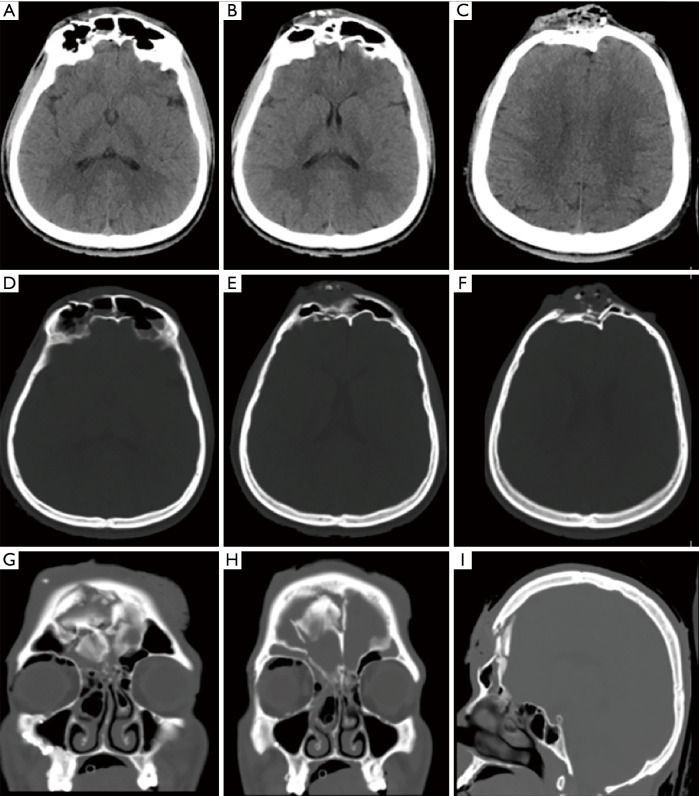

Case description: We present a 21-year-old male who was involved in an MVA with an unknown mechanism and was brought by ambulance to our emergency department at Dammam Medical Complex. Initially, the patient was vitally stable, conscious, alert, and oriented. He had multiple scalp lacerations, including a mid-forehead open wound laceration with bone fragments and some brain tissue protruding out of the lacerated wound defect. After clinical deterioration, the patient underwent an urgent surgical exploration and elevation of skull fracture along with primary skull reconstruction. The mid-forehead wound defect was repaired in collaboration with the plastic surgery team.